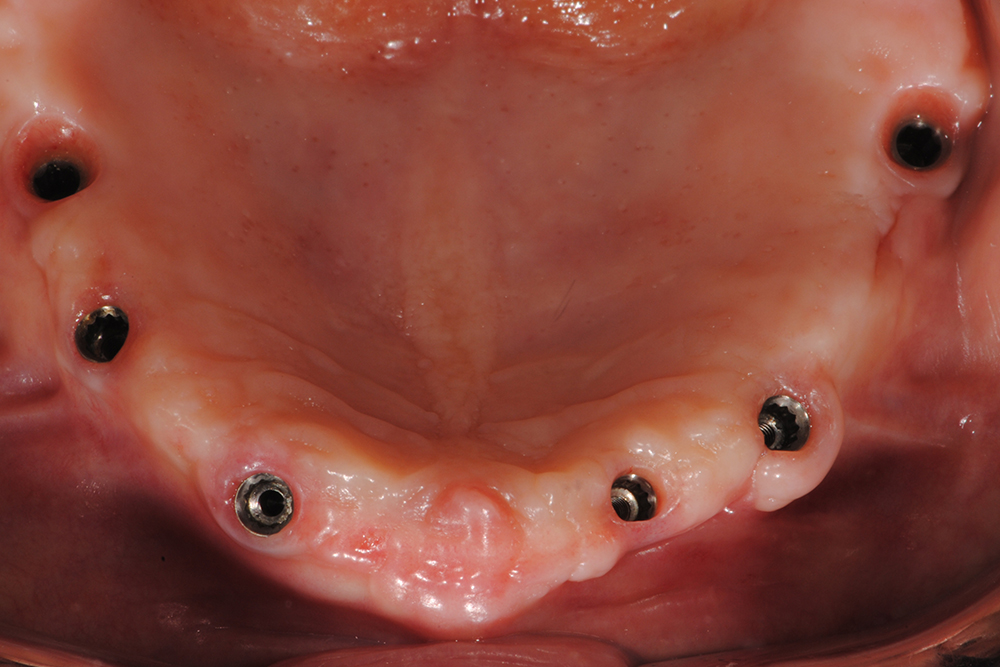

Ripristino dell'arcata superiore atrofica su impianti con ricostruzione estetica in zirconia e ceramica Category: Lavori ImpiantiMaggio 9, 2018Condividi questo ProgettoShare with FacebookShare with TwitterShare with Google+Share with PinterestShare with LinkedInProject navigationPreviousPrevious project:Ripristino dell’arcata superiore atroficaNextNext project:Ripristino dell’arcata superiore ed inferiore